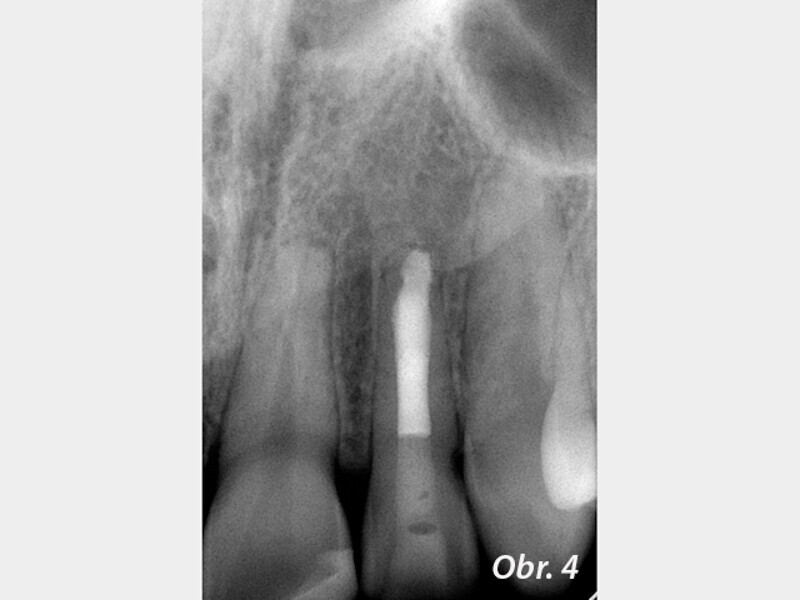

Endodontické ošetření zubů s nedokončeným vývojem kořene